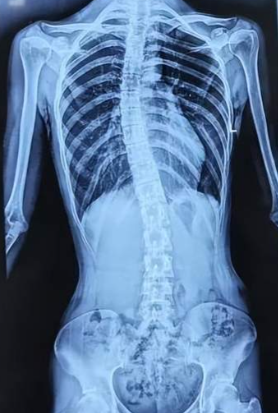

척추측만증은 척추가 좌우로 휘는 것뿐만 아니라, 척추뼈 자체가 비틀리는 3차원적인 변형을 포함합니다. 스스로 힘을 준다고 해서 바로 펴지지 않는 구조적인 변화가 특징입니다. 일반적으로 엑스레이 검사에서 휜 각도(코브 각)가 10도 이상일 때 척추측만증으로 진단합니다.

육안 검사에서 이상이 발견되면, 척추의 정확한 상태를 파악하기 위해 영상 의학적 검사를 진행합니다. 목부터 골반까지 척추 전체가 한 화면에 나오도록 촬영하는 전척추 엑스레이를 통해 휜 각도를 수치로 계산하여 심각한 정도를 체크합니다.